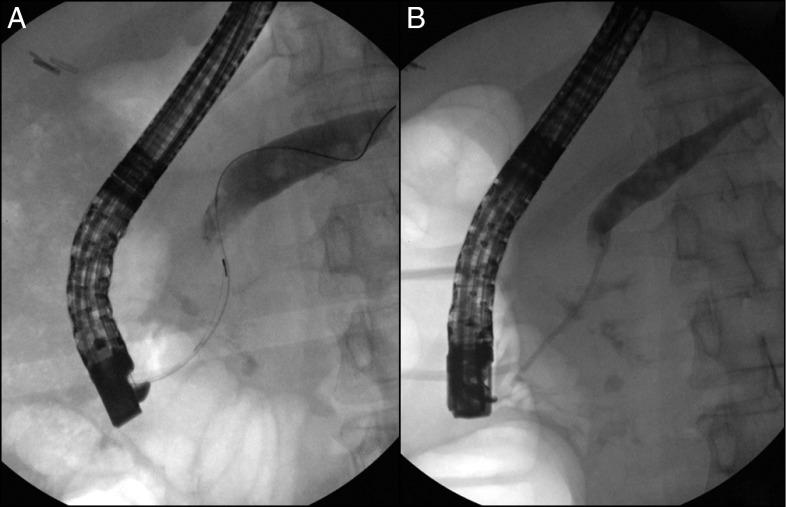

Acute obstructive suppurative pancreatic ductitis (AOSPD) is a rare clinical entity defined as suppuration from the pancreatic duct without concomitant pancreatic cyst, abscess, or necrosis. We describe a case of AOSPD in a woman with a past medical history of type 2 diabetes and chronic pancreatitis who presented with abdominal sepsis, which resolved only after therapeutic endoscopic retrograde cholangiopancreatography. Our case highlights the importance of considering AOSPD as a cause of abdominal sepsis particularly in patients with chronic pancreatitis or any recent pancreatic duct instrumentation and demonstrates that treatment requires prompt drainage and decompression of the pancreatic duct.